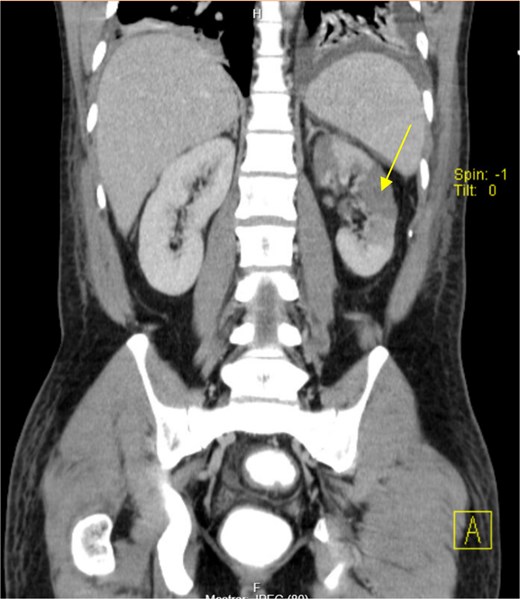

The patient presented at our Emergency Department with a sudden, diffuse, intense abdominal pain. Upon physical examination, the patient’s blood pressure was measured at 132/76 mmHg, heart rate of 103 bpm and a temperature of 39.4°C. The abdominal examination showed a rigid abdomen, with diffuse tenderness, suggesting an acute abdomen scenario. Laboratory tests revealed elevated inflammatory parameters. A abdominal and pelvic computed tomography scan revealed pneumoperitoneum and free fluid in the right iliac fossa and pelvis (Fig. 1). An exploratory laparotomy was proposed and the intraoperative findings included a sigmoid colon perforation with faecal peritonitis. They proceed with sigmoidectomy and temporary abdominal closure, planning for a reintervention to restore gastrointestinal continuity. This was done, after 48 h, through mechanical latero-lateral colo-colic anastomosis. The histopathological examination confirmed diverticulosis with perforation. The patient was subsequently transferred to the intensive care unit, for 5 days. Posteriorly, he developed severe left lumbar pain and hypertension unresponsive to medication. A CT scan revealed left kidney acute ischemia due to left renal artery thrombosis (Fig. 2). Broad-spectrum antibiotic therapy and anticoagulation, was initiated, after assessment by the Vascular Surgery and Urology teams. During his hospitalization, the patient experienced additional thrombotic events, such as occlusion of the left radial artery, and right lower lobar pulmonary embolism. A workup for prothrombotic conditions was conducted, including tests for thrombophilia, lupus, cardiolipins, antinuclear antibody, total protein test, and immunoglobulins, all of which were negative. An angiography of the abdominal aorta revealed arterial microaneurysms in the splanchnic territories: hepatic, perigastric and mesenteric arteries, suggesting polyarteritis nodosa (Fig. 3). Echocardiogram showed no abnormalities. The patient also underwent a study of the left shoulder due to repetitive pain complaints, with a suspected rupture of the rotator cuff. Electromyography excluded peripheral nerve damage. No other complications were reported. The patient was discharged on the 21st day after surgery, under anticoagulation therapy and steroids due to a suspected diagnosis of polyarteritis nodosa. Twenty-seven days after surgical intervention, the patient returned to the ED, presenting with abdominal pain in the lower quadrants and nausea. He was hemodynamically stable with abdominal pain and tenderness on the left flank and iliac fossa. Laboratory tests revealed leukocytosis and hyperlactacidemia. The CT scan reported free fluid, free gas bubbles adjacent to the sigmoid which had a concentric circular thickening of the wall, just distal to the previous anastomosis (Fig. 4). An exploratory laparotomy was performed, during which a large hematoma on the wall of the left colon was identified, with no apparent signs of perforation. A peritoneal lavage, drainage, and a derivative ileostomy were carried out. During the post-operative period the patient maintained a small volume of purulent discharge through the abdominal drain, with no abdominal tenderness. A reevaluation CT scan was performed, highlighting a regression of the hematoma of the colonic wall but raised suspicion of a low output fistula near the anastomosis. Since the patient maintained hemodynamic and analytical stability, he was discharged from the hospital with home care, including an abdominal drain, parenteral nutrition, empirical antibiotic therapy, and gradual reduction in the steroid dosage. The patient was referred to the ED, on Day 6, due to enteric drainage. An enterocutaneous fistula was diagnosed, and he was readmitted. He received 12 days of full-dose parenteral nutrition, which reduced the fistula output and improved his clinical and analytical status. Due to residual drainage volume and an analytical and imagiologic improvement, the drain was removed, and the patient was discharged, tolerating an oral diet, and with a functioning ileostomy.